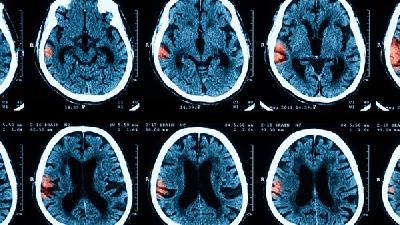

少儿良性癫痫日常需注意规律作息、避免诱因、定期复查、心理疏导四个方面。该病预后良好,多数患儿青春期后可自行缓解。

即使无发作症状,家长也须每3-6个月带孩子进行脑电图检查。医生可能根据情况调整丙戊酸钠、左乙拉西坦等抗癫痫药物用量。